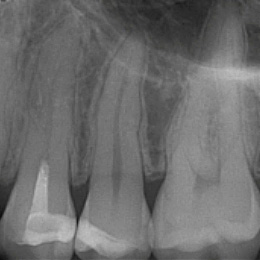

Fallbeispiel: Revision 46 (und 45) Recall 6 Monate

Bringt eine Wurzelkanalbehandlung nicht den gewünschten Erfolg, bedeutet dies nicht, dass ein Zahn nicht mehr zu erhalten ist. Mit einer Revisionsbehandlung können auch bereits wurzelkanalbehandelte Zähne langfristig erhalten werden!